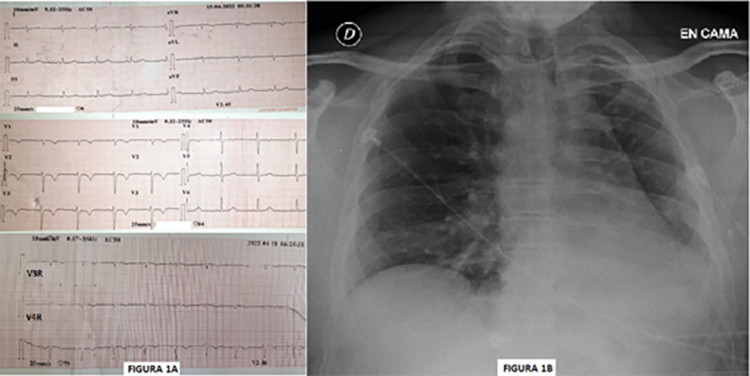

El electrocardiograma muestra ritmo sinusal, 65 lpm, eje vertical y trastorno de repolarización ventricular antero septal, correspondiente a ventrículo derecho. (Figura 1A). La radiografía de tórax de frente evidencia sombra hiliar ausente y desplazamiento del mediastino del lado izquierdo con elevación del hemidiafragma de ese lado e hiperinsuflación del pulmón contralateral. (Figura 1 B)